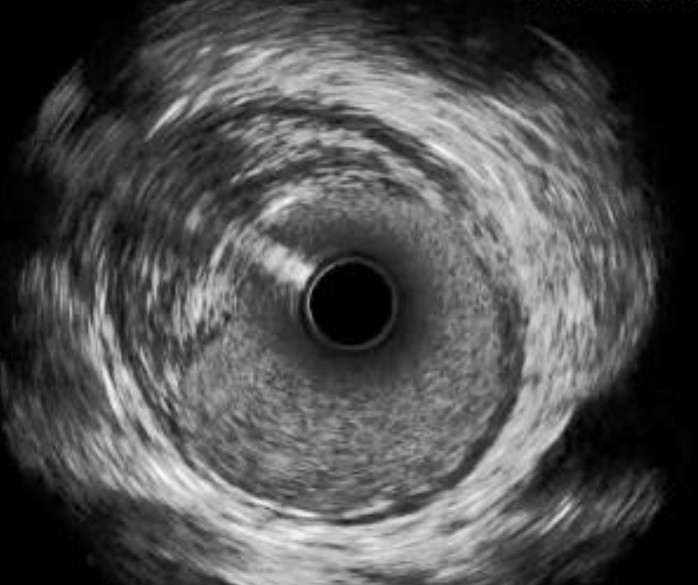

OPTICROSS HD Imaging Catheter vs. Competitor

High-Definition IVUS image quality helps physicians more accurately identify lesion length, assess plaque morphology, and determine the tools required for vessel prep. See how OPTICROSS HD’s 60 MHz images stack up against the competition.

OPTICROSS Imaging Catheter 40 MHz

IVUS image of inside a coronary vessel using the 40MHz Opticross catheter

Axial resolution: 38 µm

OPTICROSS versus OPTICROSS HD images courtesy of Michael Kim, MD, FACC, FSCAI North Colorado Medical Center